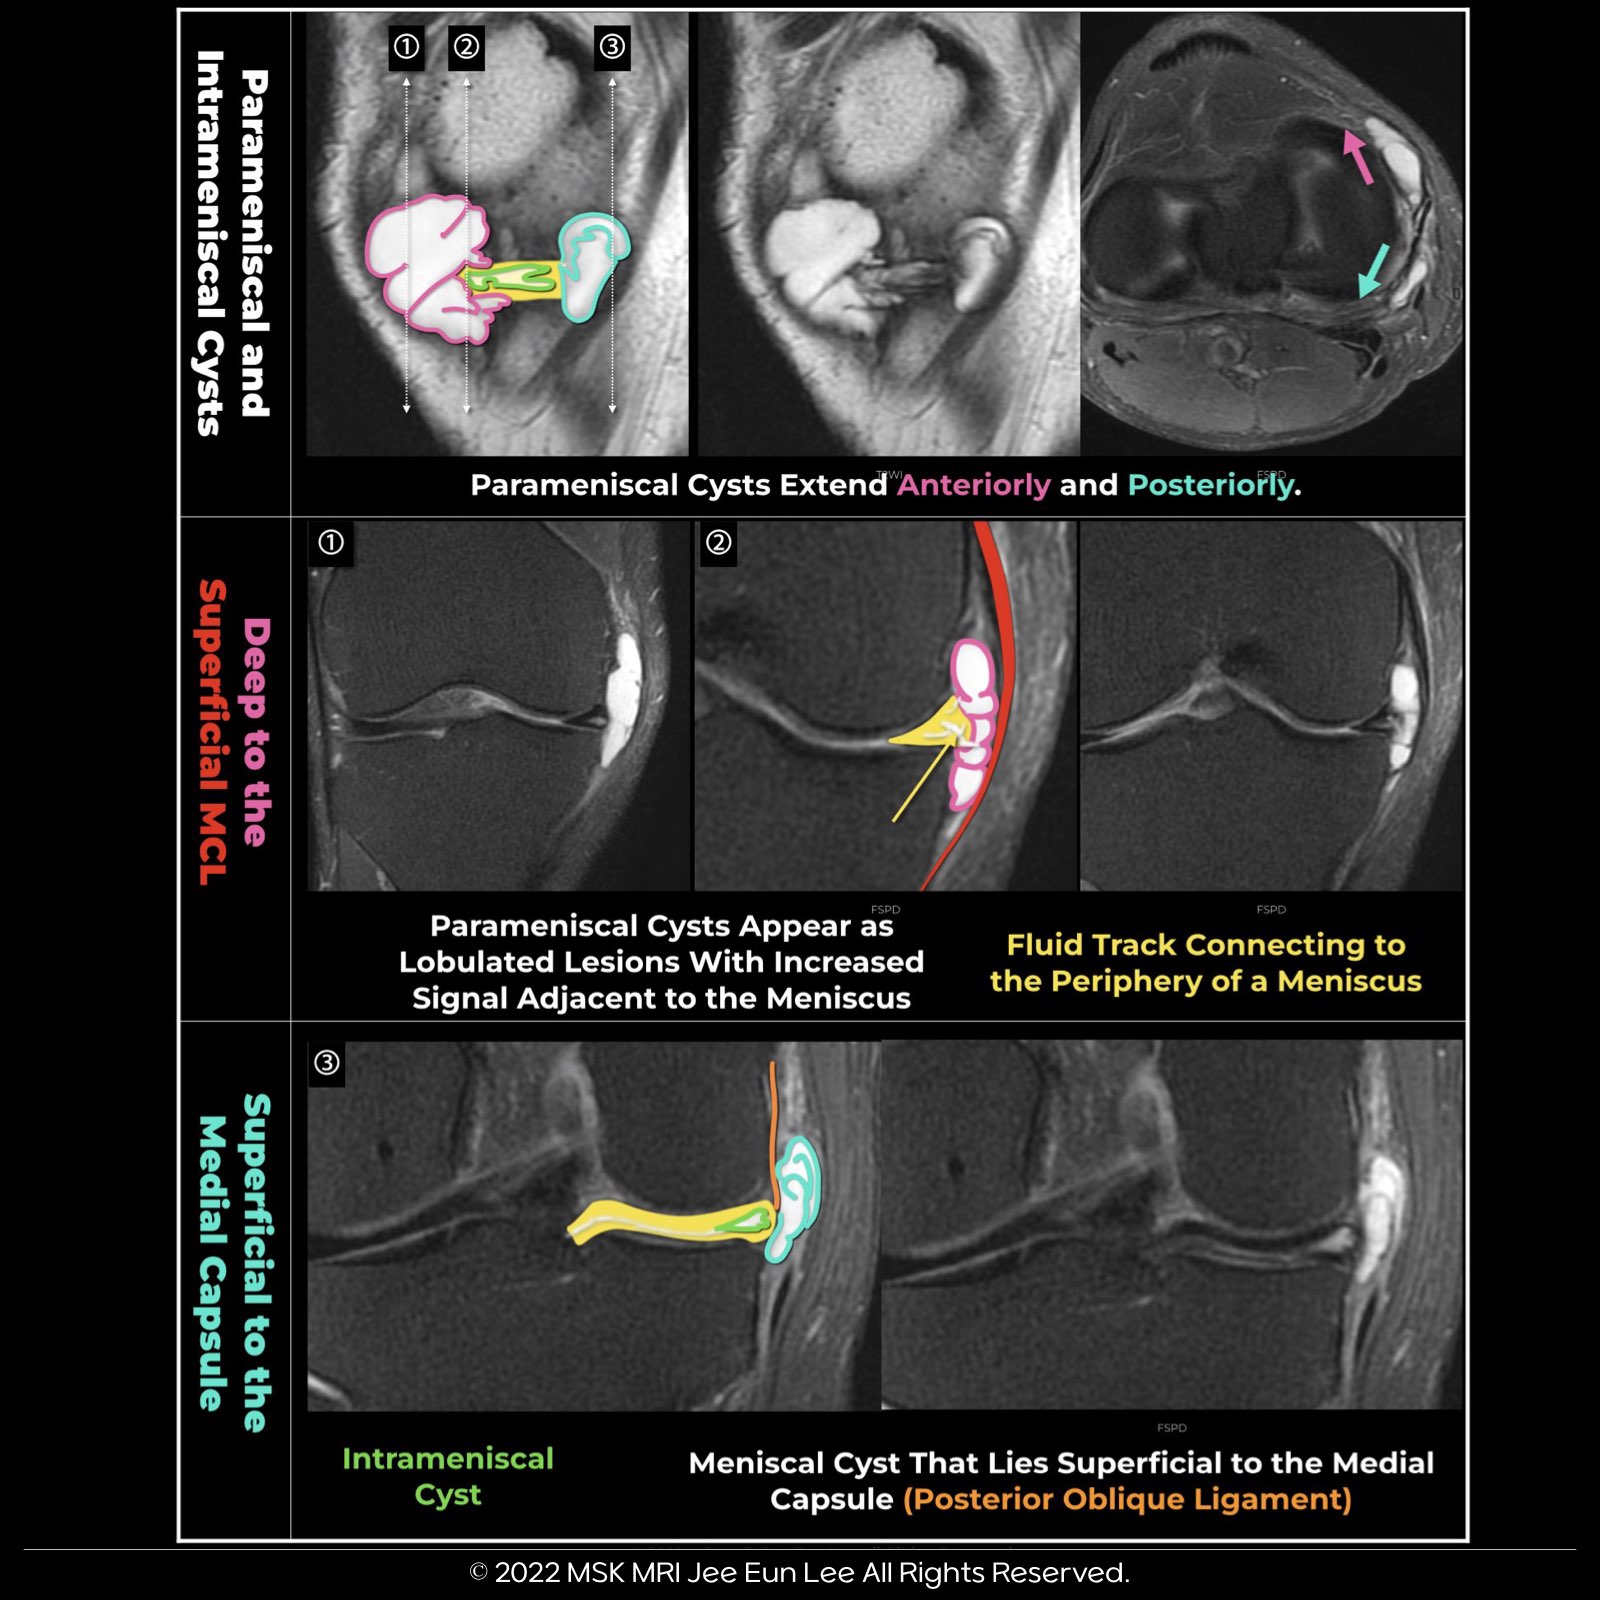

1️⃣ Intrameniscal Cysts:

- Appear as an increased signal within an enlarged meniscus.

2️⃣ Parameniscal Cysts:

- Appearance: Lobulated lesions with increased signal adjacent to the meniscus.

- Location: May extend along tissue planes.

✅ Medial Cysts:

- Can extend anteriorly to lie superficial to the Medial Collateral Ligament (MCL).

✅ Lateral Cysts:

- May extend anteriorly to lie deep to the iliotibial band and posterolaterally to lie deep to the Lateral Collateral Ligament (LCL).

3️⃣ Parameniscal Cyst Specifics on T2-weighted Imaging:

- It is defined as a high-signal-intensity fluid collection either directly overlying a meniscus or adjacent to a meniscus with a fluid track connecting to the periphery of a meniscus.